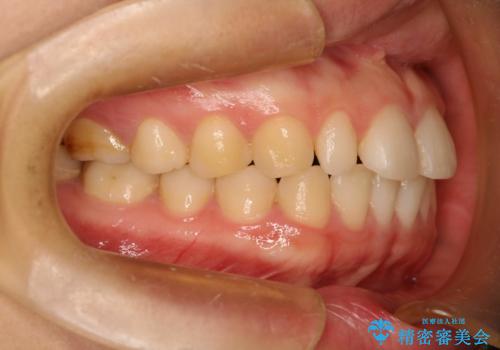

Invisalign インビザライン lite ライト 隙っ歯の改善

- マウスピース矯正による隙間の閉鎖を計画しました。

簡便な処置のため、ライトを選択しました。

かみ合わせが深くない空隙歯列は、最も簡単にその改善が見込まれます。